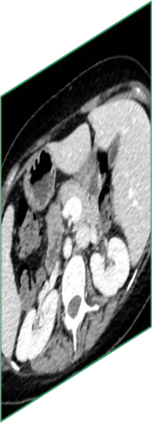

Due to the constraints of the imaging device and high cost in operation time, computer tomography (CT) scans are usually acquired with low intra-slice resolution. Improving the intra-slice resolution is beneficial to the disease diagnosis for both human experts and computer-aided systems. To this end, this paper builds a novel medical slice synthesis to increase the between-slice resolution. Considering that the ground-truth intermediate medical slices are always absent in clinical practice, we introduce the incremental cross-view mutual distillation strategy to accomplish this task in the self-supervised learning manner. Specifically, we model this problem from three different views: slice-wise interpolation from axial view and pixel-wise interpolation from coronal and sagittal views. Under this circumstance, the models learned from different views can distill valuable knowledge to guide the learning processes of each other. We can repeat this process to make the models synthesize intermediate slice data with increasing inter-slice resolution. To demonstrate the effectiveness of the proposed approach, we conduct comprehensive experiments on a large-scale CT dataset. Quantitative and qualitative comparison results show that our method outperforms state-of-the-art algorithms by clear margins.